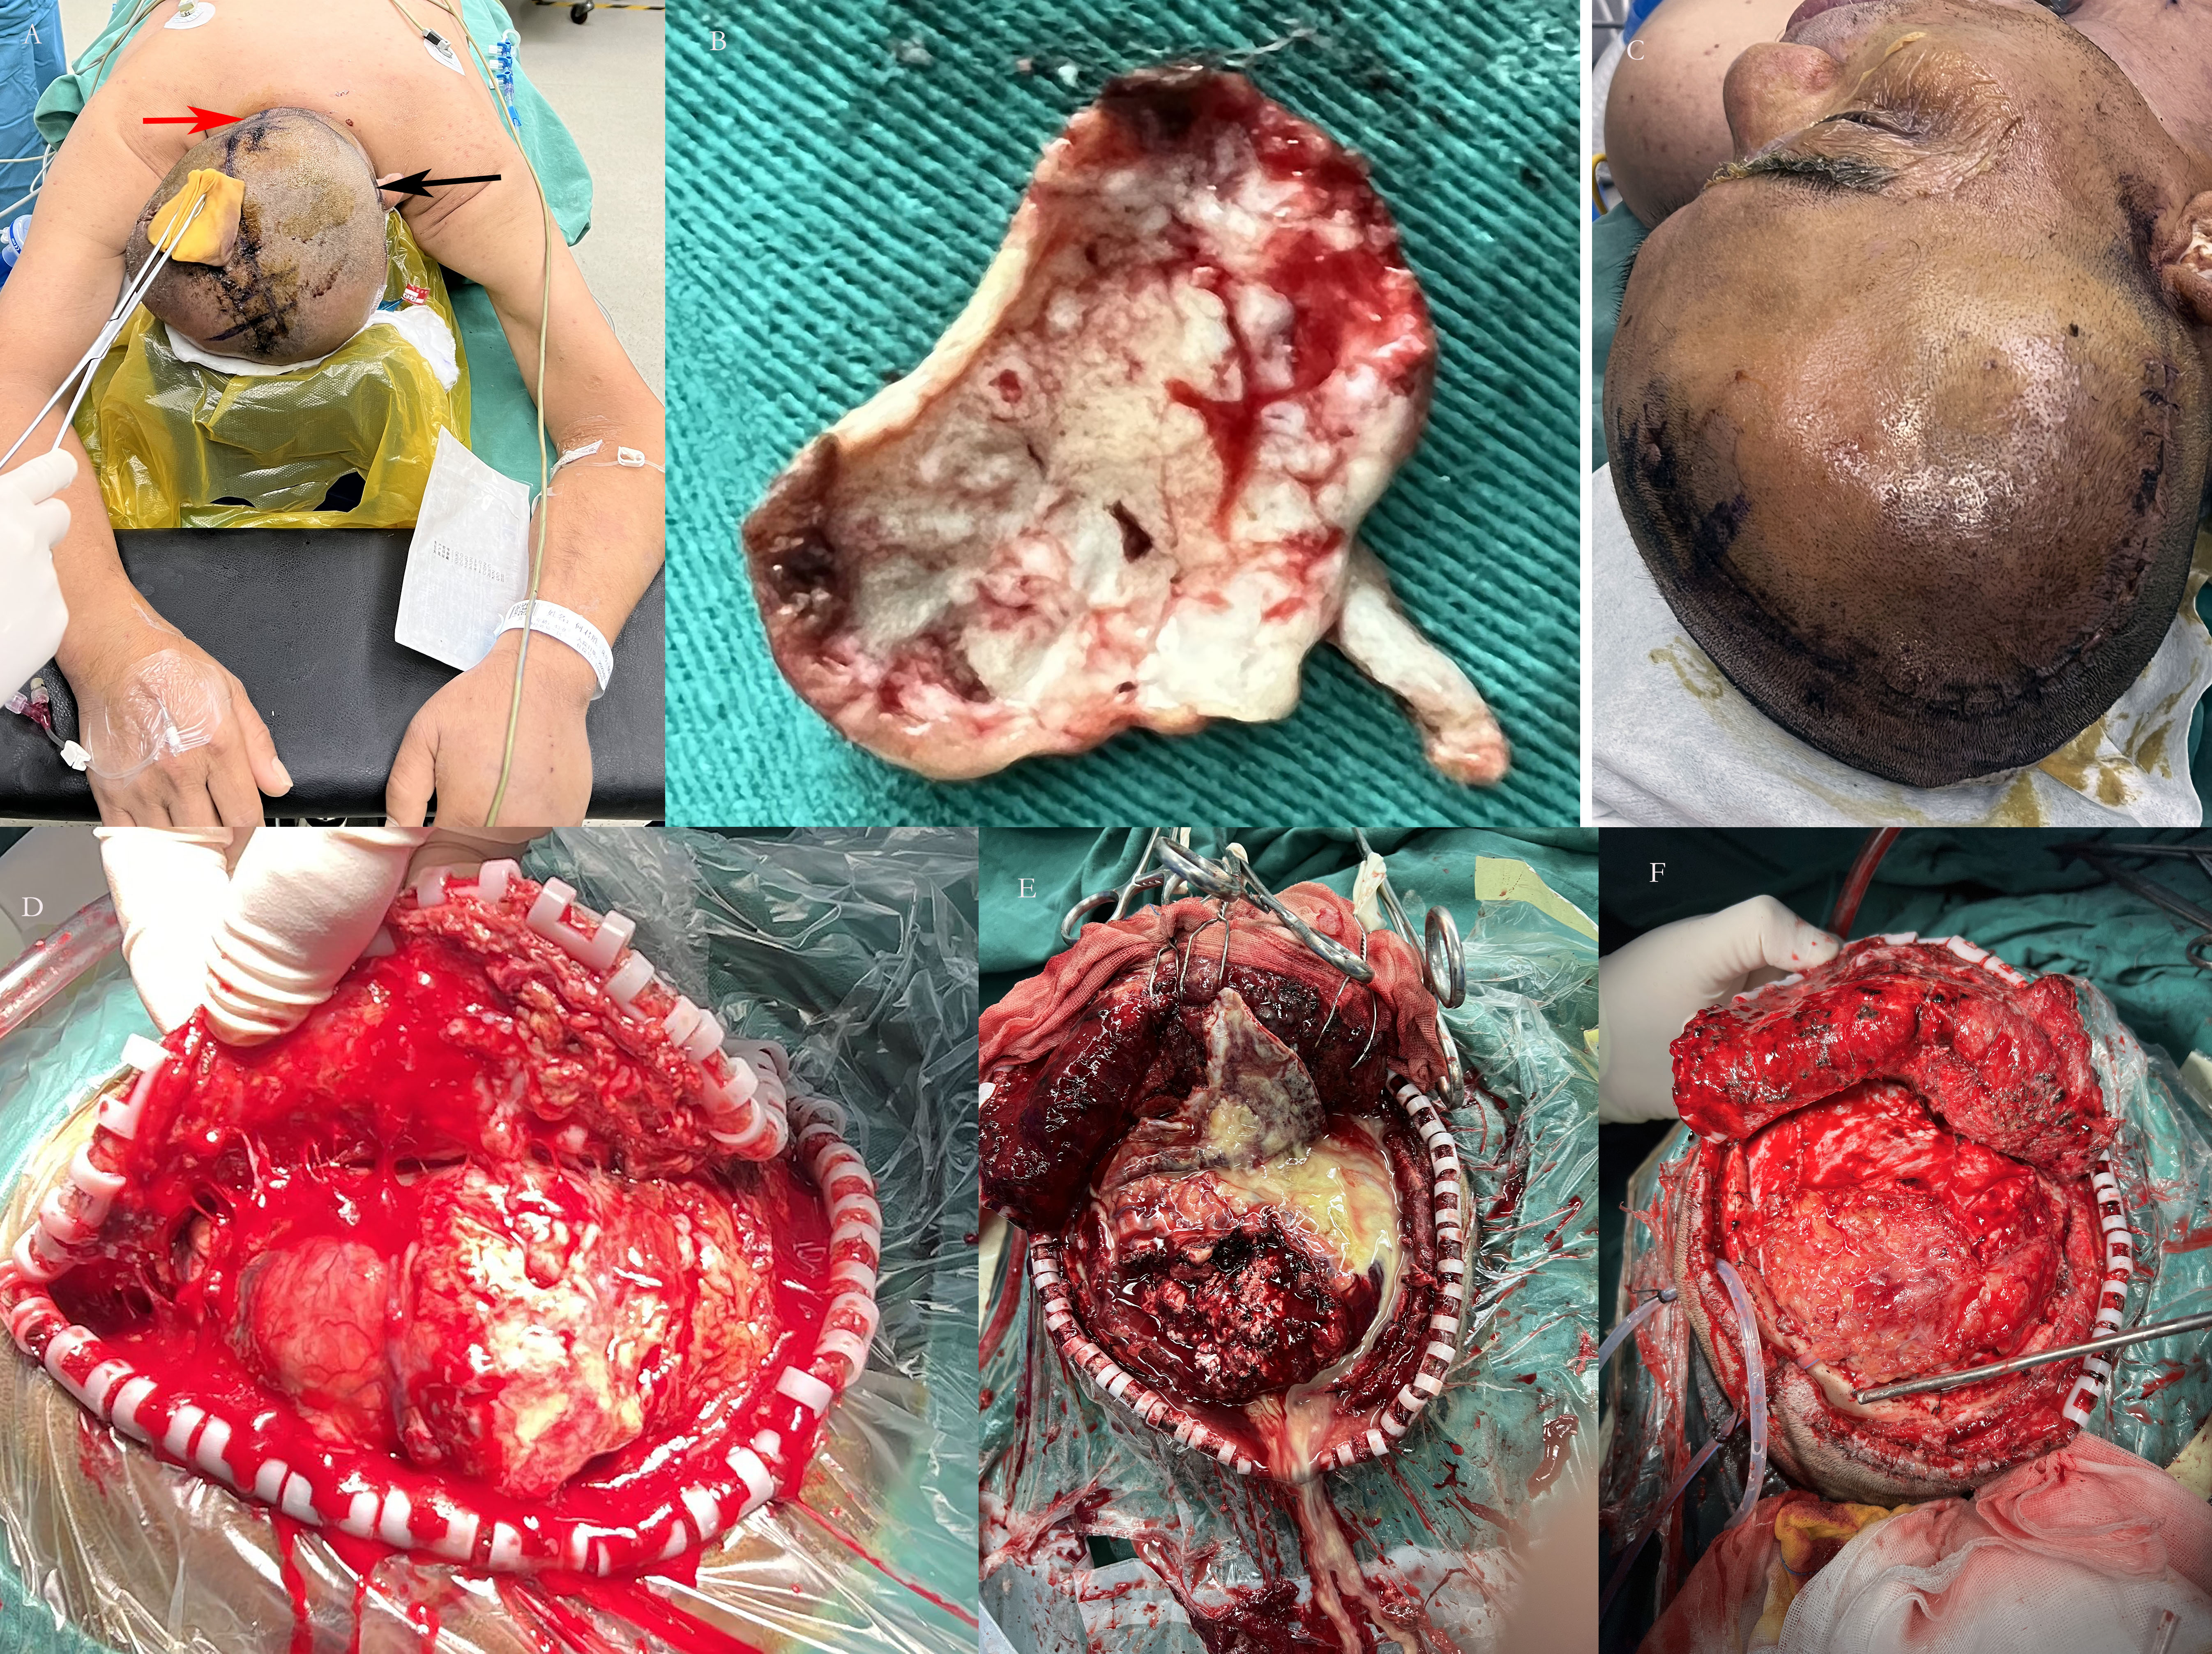

2023-08-04头皮切口张力高,脑脊液漏,脓性分泌物流出。MRI可见左顶、左额、左枕、左颞、右额颞枕共5处脑脓肿,右侧额颞枕脓肿可一次手术切除,但其余4处需要分开开颅切除脓肿,先俯卧位,切除左顶、左额、左枕、左颞脓肿,后仰卧位,切除右侧额颞枕脓肿,术前取右侧大腿阔筋膜作为修补脑脊液漏。

2023-08-04日在全麻下内多发脑脓肿切除术。